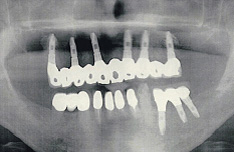

治療前のパノラマX線写真

右上の前歯の治療を希望し、紹介を受け来院された患者さんです。

この歯[A]は子供の時に転んでぶつけ、根の治療がされていましたが、レントゲン上で見ると、根の途中部分の外側から吸収が始まってきていました。

(※外傷歯について:歯をぶつけるなど、強い衝撃が与えられた場合、無症状に経過していても数年後に歯根の異常吸収や骨との癒着が起きることがあります。)根の一部を切除して歯を残せる場合もありますが、今回は残念ながら抜歯となりました。 左の口腔内写真は、抜歯直後の状態です。